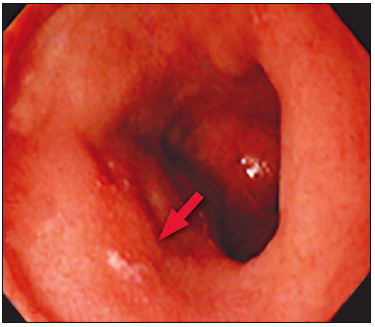

En la VEDA se observó gastropatía eritematosa leve; la VCC mostró una mucosa colónica

normal, sin lesiones. No se logró realizar la intubación ileal debido a la estenosis de la válvula ileocecal

(Figura 3).

Figura 3. Estenosis de válvula ileocecal. A. VIC, B.

ciego